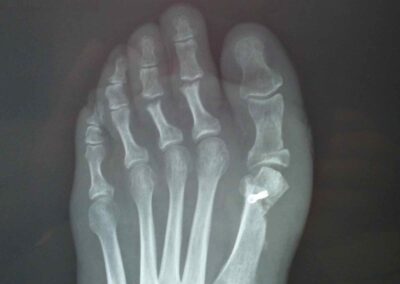

E’ frequente specie nelle donne e prevede, quando indicato, un trattamento chirurgico. E’ importante considerare univocamente anche le patologie eventualmente associate dell’avampiede e del retropiede per una corretta indicazione chirurgica. Lo studio clinico poi deve essere integrato da una radiografia dei piedi in comparativa e sotto carico gravitario.

Il problema della chirurgia riparativa dell’ alluce valgo è la recidiva della deformità che addirittura è meno grave della ipercorrezione con conseguente alluce varo secondario. Occorre dunque programmare le osteotomie eventualmente associate alla testa del primo metatarso ed alla base della prima falange con un accurato planning preoperatorio in base a parametri morfologici da ricercare in una radiografia preoperatoria eseguita sotto carico gravitario.E’ fondamentale associare un riequilibrio delle parti molli capsulari e tendinee che andranno opportunemente adattate alla nuova configurazione geometrica dell’avampiede.Sarà poi importante l’ausilio di bendaggi o taping nelle prime settimane postoperatorie a mantenere la correzione ottenuta fino alla completa guarigione delle correzioni ossee e delle parti molli.Preciso che è fondamentale seguire l’evoluzione della cicatrizzazione con controlli ogni due settimane nei primi 45gg postoperatori con possibilità di correggere con adeguati taping eventuali iper piuttosto che ipo correzioni.